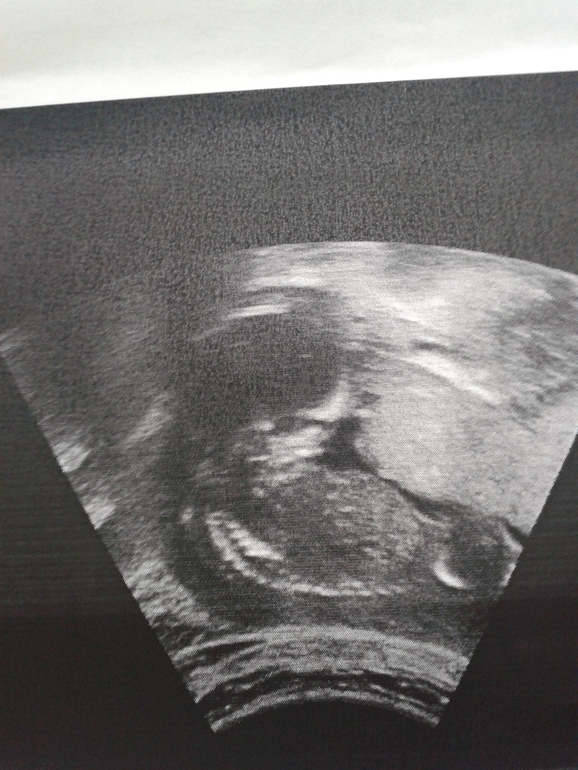

И меня очень напрягло что ребенок лежит скрючено,вот фото. Было ли у кого так?

Поздравляю с экватором! =) Деть лежит как удобно..по моему ничего такого особенного в позе нет. С плацентой не скажу..не знаю.

По поводу положения ребенка не переживайте, он лежит, как ему удобно и это влияет лишь на красоту фото. Утолщение плаценты может говорить об инфекции. С этим вопросом ко врачу, здесь такие серьезные вопросы не советую решать, накрутите лишнего на мозг себе.Желаю чтобы все было хорошо с Вами и малышом